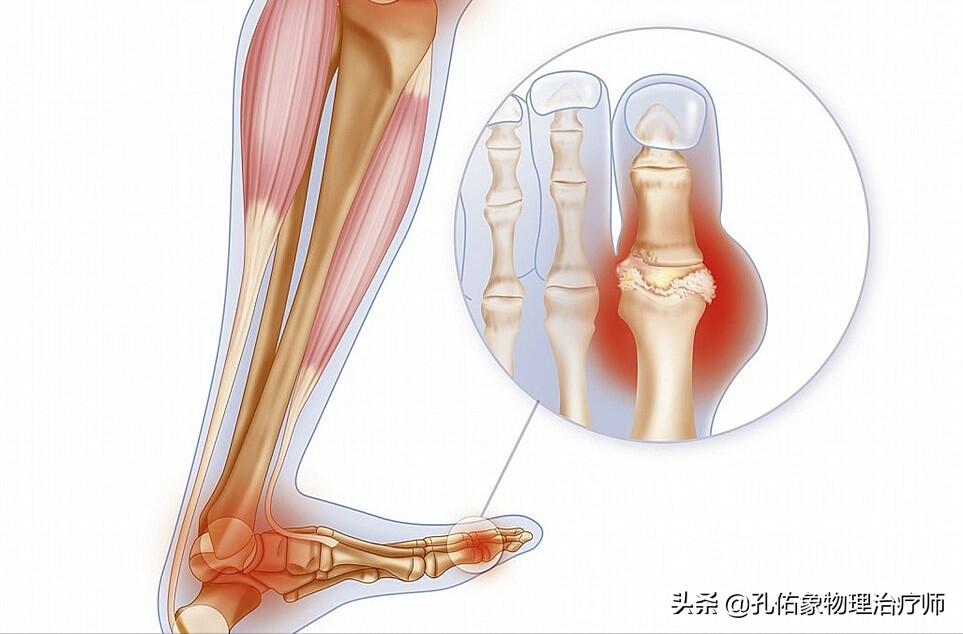

6.痛风

目前,发生痛风的人也越来越多了,一般多见于30-45岁左右,男性居多;若是当尿酸高到一定程度,就会引发大脚趾关节、脚踝、脚后跟等部位疼痛。

但是有一部分人会忽略这个问题,前久遇到一个本院的主任,它就是大脚趾下方疼痛,走路都一瘸一拐的,还想着是自己锻炼时,蹬动感单车扭到了,最终让他去检查,结果是痛风所致。